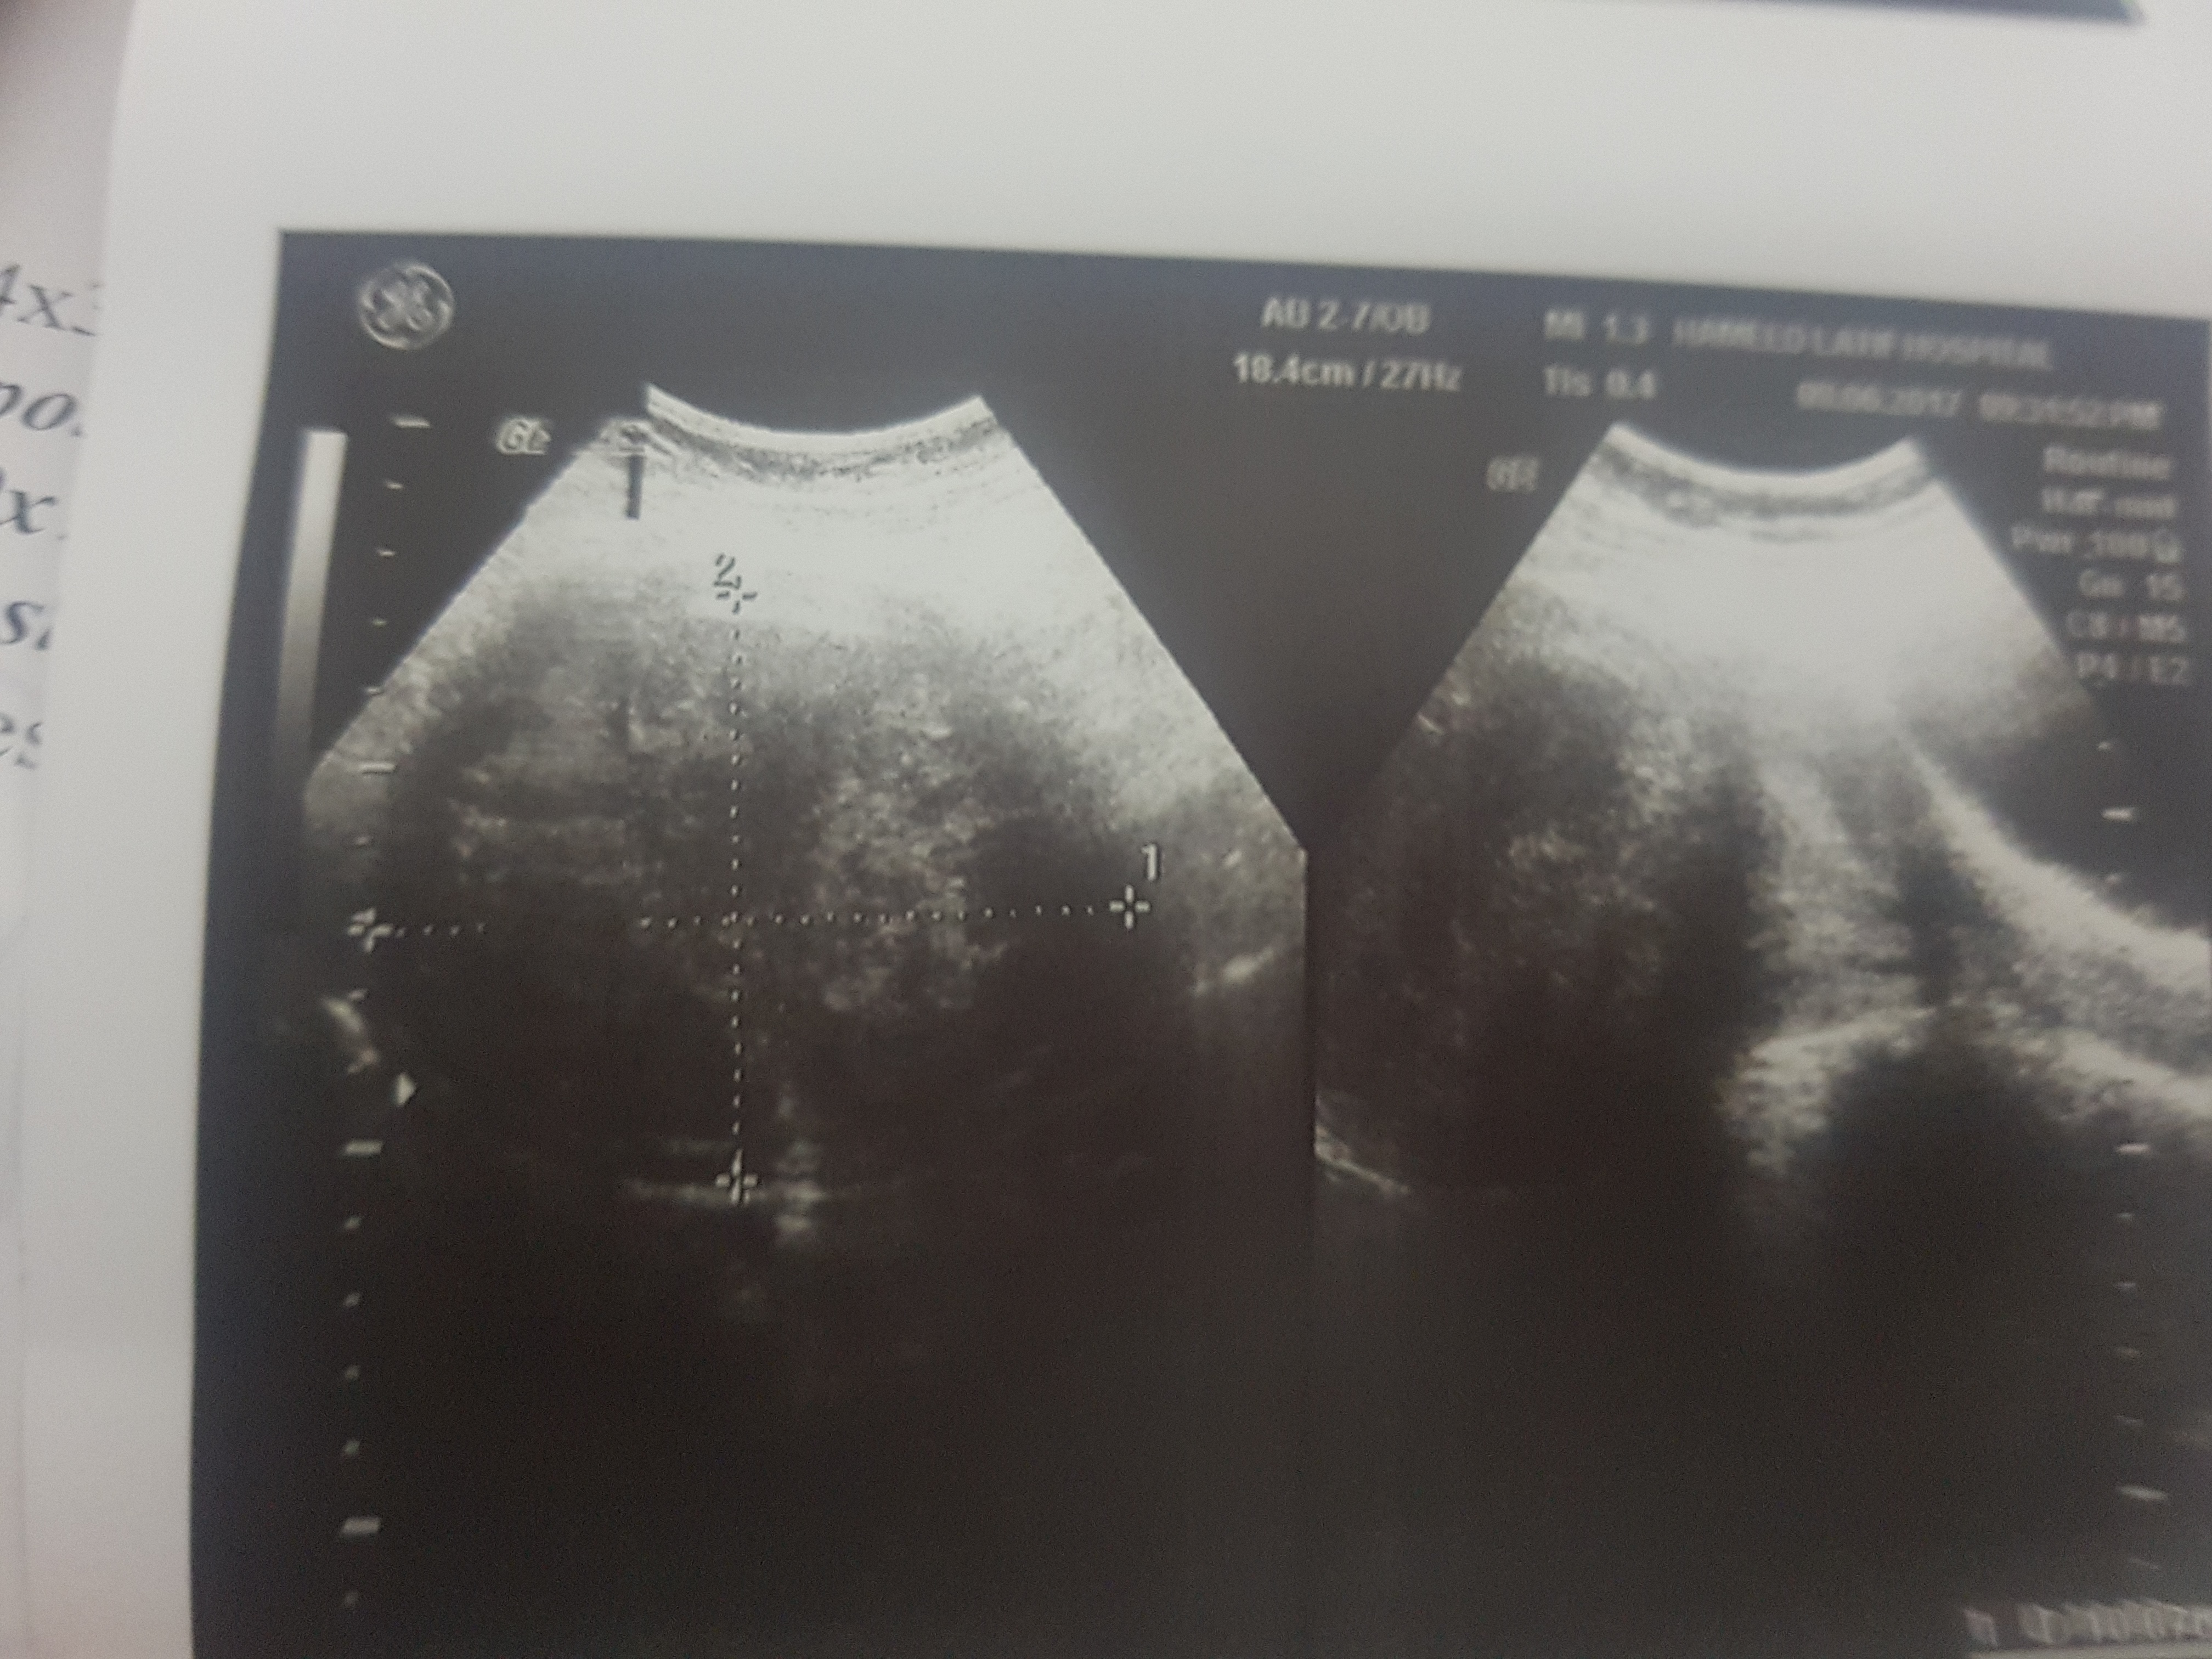

these r my ultrasound report should i go for surgery?? ak br mai ny expect kia ha par result was explusion in 24 weeks plzz guide me im not conceiving again

ak dafa mai ny conceive kia tha 24 weeks mai explusion 6 mnths phly hwa tha us k bd abi tk concieve nai says k take 1 more chance.. surgery k bd conpliction hti ha conceive krny mai